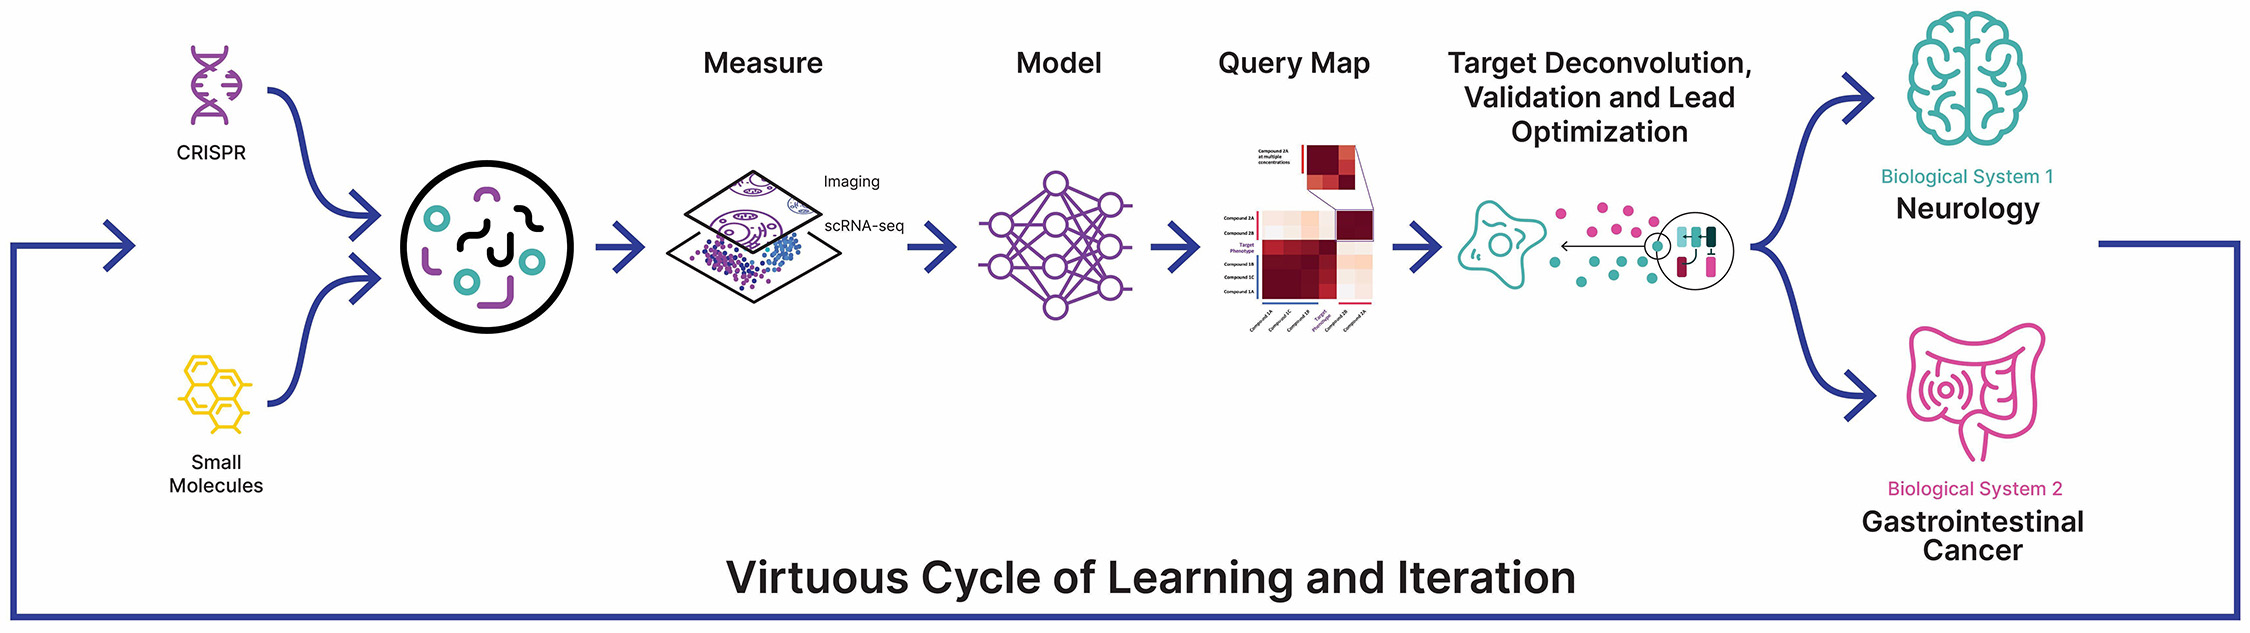

Figure 1. A simple formula is used across technology industries to map and navigate complex systems. First, high-dimensional data is generated, aggregated and organized to create digital representations. Then, AI/ML algorithms make predictions about that system that can be tested in reality. The result is a virtuous cycle of learning and iteration.

At Recursion, we are pioneering the integration of innovations across biology, chemistry, automation, data science and engineering to industrialize drug discovery in a full-stack solution across dozens of key workflows and processes critical in discovering and developing a drug. For example, by combining advances in high content microscopy with arrayed CRISPR genome editing techniques, we can rigorously profile massive, high-dimensional biological and chemical perturbation libraries in multiple human cellular contexts to create digital ‘maps’ of human biology. Leveraging advances in scaled computation, we can conduct massive virtual screens to predict the protein targets for billions of chemical compounds. Similarly, data generated from our automated DMPK module and InVivomics platform enables us to predict ADME properties and identify toxicity signals, respectively, significantly faster than traditional methods. We believe that by harnessing advances in technology to industrialize drug discovery, we can derive novel biological insights not previously described by scientific researchers, reduce the effects of human bias inherent in discovery biology and reduce translational risk at the program outset.